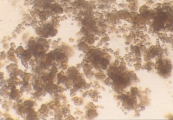

УРАТЫ АММОНИЯ И АМОРФНЫЕ УРАТНЫЕ КРИСТАЛЛЫ Особенности Кристаллы урата аммония (также наываемые биурата аммония) обычно обнаруживаются в слегка закисленной, нейтральной или щелочной моче. Они, как правило, желтого или желто-коричневого цвета, сферической формы с длинными иррегулярными выступами (так называемое колючее яблоко) (рис. 43-51). Соли уратов натрия, калия, магния могут преципитировать в виде аморфных образований в кислой моче (так называемые аморфные ураты). Они могут напоминать аморфные фосфаты (рис. 49), но способны растворяться в щелочной среде. При росте аморфных кристаллов (рис. 47-51) они приобретают желтую или желто-коричневую окраску. Ураты натрия могут преципитировать как бесцветные или желтоватые иголочки или как тонкие призмы в связке или пучках (рис. 52-56). Ураты аммония и аморфные кристаллы урата нерастворимы в кислой моче. Однако, добавление 10% уксусной кислоты в мочевой осадок, содержащий эти кристаллы, часто приводит к выделению мочевой кислоты и иногда кристаллов натрия урата. Добавление уксусной кислоты к аморфным кристаллам фосфата приводит к их быстрому растворению, в то время как они продолжают сохраняться в осадке щелочной мочи. Интерпретация Аммония ураты и аморфные ураты могут встречаться у, по-видимому, нормальных собак и кошек. Часто они обнаруживаются у собак с портальными сосудистыми аномалиями с или без сопутствующими аммоний уратными уролитами. Также они распространены среди далматинов, английских бульдогов и других собак и кошек по причинам, несвязанным с портальными сосудистыми аномалиями. Рис. 43. Микрофотография кристаллов аммония урата (форма колючего яблока) в мочевом осадке 3-летнего кобеля английского бульдога с аммоний уратными камнями в мочевом пузыре (не окрашено, увеличение Х 250). Рис. 44. Микрофотография кристалла аммония урата в виде колючего яблока в мочевом осадке 7-месячного йоркширского терьера с портальной сосудистой аномалией (не окрашено, увеличение Х 250). Рис. 45. Сканированная электронная микрофотография кристалла, описанного в рис.44 (увеличение Х 2,880). Рис. 46. Микрофотография кристаллов аммония урата в мочевом осадке годовалой самки Персидской кошки с портальной сосудистой аномалией (не окрашено, увеличение Х 128). Рис. 47. Микрофотография рыжевато-коричневых аморфных кристаллов аммония урата и кристаллов магний аммоний фосфата в мочевом осадке 3-летнего кобеля английского бульдога с аммоний уратными камнями в мочевом пузыре (не окрашено, увеличение Х 128). Рис. 48. Сканированная электронная микрофотография кристаллов, описаных в рис. 43, 47 (увеличение Х 8,640). Рис. 49. Микрофотография аморфных кристаллов аммония урата в мочевом осадке 7-летнего аляскинского маламута с аммоний уратными камнями в мочевом пузыре (не окрашено, увеличение Х 128). Рис. 50. Сканированная электронная микрофотография аморфных кристаллов аммония урата, смежных с кристаллами мочевой кислоты в закисленном мочевом осадке собаки, описанной в рис. 49 (увеличение Х 5,400). Рис. 51. Микрофотография аморфных кристаллов аммония урата в мочевом осадке собаки, описанной в рис. 44 (не окрашено, увеличение Х 250). Рис. 52. Микрофотография кристаллов натрия урата в мочевом осадке собаки, описанной в рис. 49 (не окрашено, увеличение Х 128). Рис. 53. Микрофотография рыжевато-коричневых кристаллов натрия урата, кристаллов магний аммоний фосфата и кристаллов кальция оксалата дегидрата в мочевом осадке собаки (не окрашено, увеличение Х 51). Рис. 54. Микрофотография кристаллов аммония урата в мочевом осадке собаки, описанной в рис. 43 (не окрашено, увеличение Х 40). Рис. 55. Микрофотография кристалла в мочевом осадке собаки, описанной в рис. 43 и 54 после добавления 10% уксусной кислоты (не окрашено, увеличение Х 250). Рис. 56. Сканированная электронная микрофотография кристаллов натрия урата в закисленном мочевом осадке собаки, описанной в рис. 43,54 и 55. Обратите внимание на маленький в форме алмаза кристалл (увеличение Х 2,340).